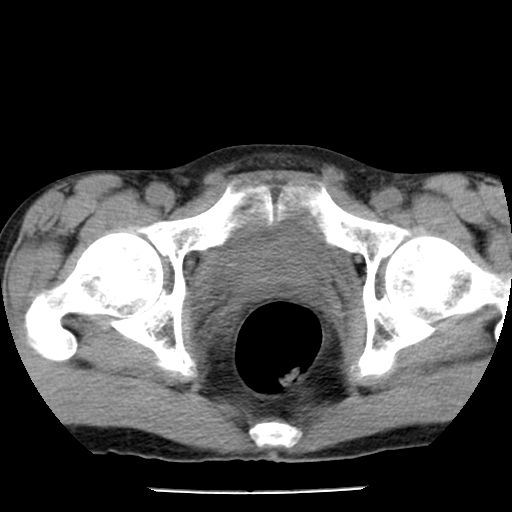

男,59岁,“结核性胸膜炎”30余年,胸部经常疼痛,多次x检查提示“肺部”炎症。腹部疼痛5日,b超提示:“肝内短管结石,余显示不清,建议进一步检查。”

两肺结核并右侧胸腔积液;脾脏、腹腔及腹膜后淋巴结结核[陈旧性];肝内胆管结石

胸部腹部都是结核(双肺。纵隔淋巴结,肝脏,脾脏,肠系膜)

两肺结核并右侧胸腔积液;脾脏、腹腔及腹膜后淋巴结结核[陈旧性];肝内胆管结石。直肠息肉?